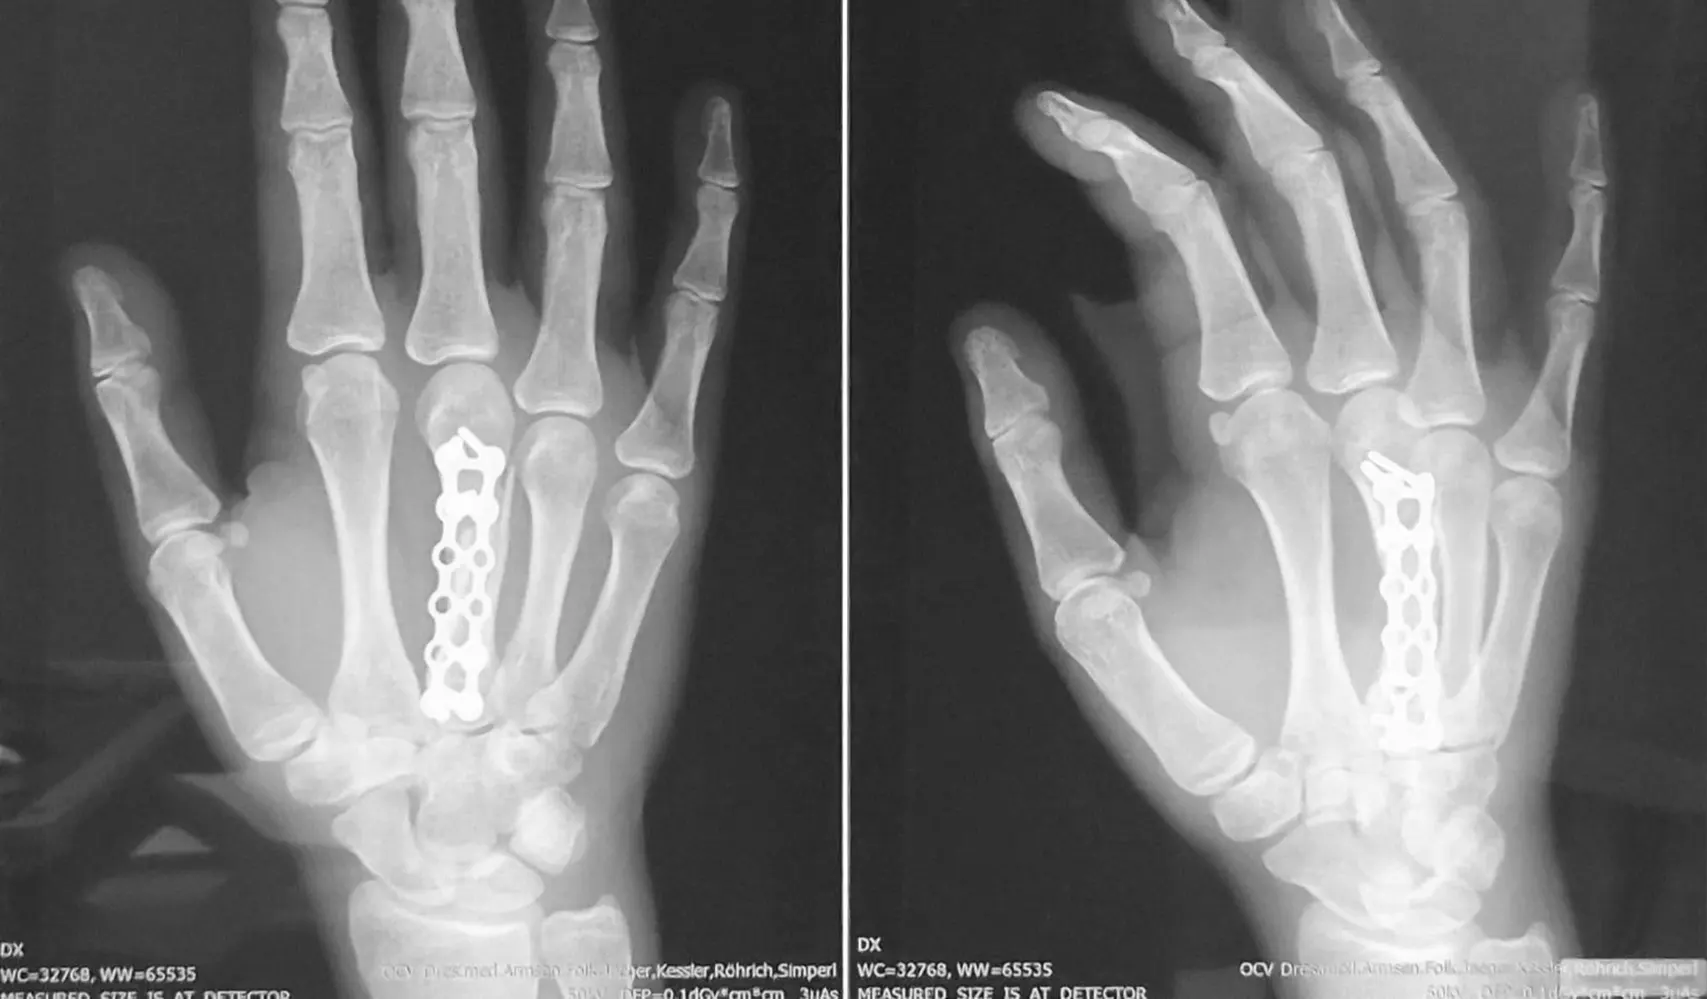

Nach Mittelhandfraktur, Operation und konsequenter Reha stand Annika beim entscheidenden Qualifikationswettkampf kurz vor den Olympischen Spielen am Start – der ersten und zugleich letzten Chance auf das Ticket.